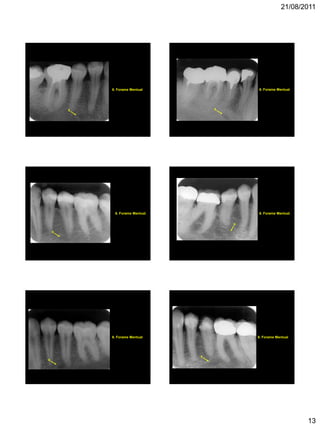

REGIÃO DE PRÉ-MOLARES

INFERIORES

2. Canal da Mandíbula

4. Base da Mandíbula

6. Forame Mentual

6

2

4